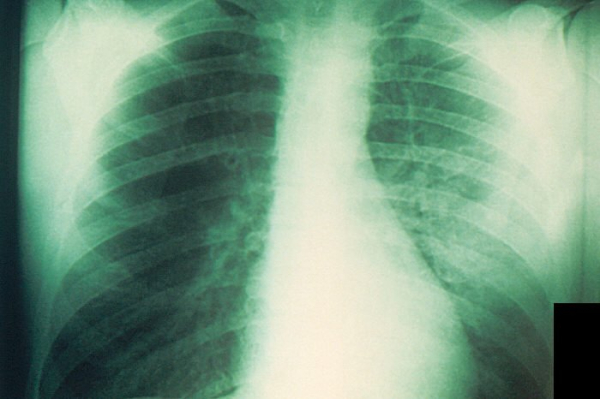

Researchers pitted 72 radiologists against four AI tools in an analysis of more than 2,000 X-rays. The human experts won. Image courtesy of the Public Health Image Library

Researchers pitted 72 radiologists against four commercially available AI tools in an analysis of more than 2,000 X-rays. The human experts won, according to results published Monday in Radiology. Advertisement